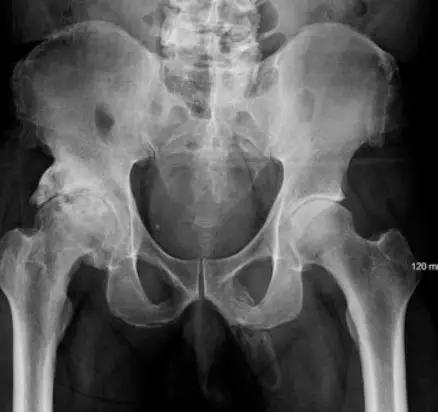

1、阴茎骨化

一位63岁的男子因膝盖受伤后去医院检查,医生无意间发现他的阴茎已经开始变成骨头,也就是钙盐在阴茎软组织中累积发生了骨化。

这种情况非常罕见,医学文献报道少于40例。

至于为什么会出现阴茎骨化,现在还不是很清楚。但是医生认为与佩罗尼氏病有关,该病表现为在海绵体的白膜有纤维无弹性的瘢痕形成,导致器官弯曲,甚至引起勃起障碍和阴茎疼痛。

然而,佩罗尼氏病不是唯一的解释,这种病也可能与代谢性疾病、终末期肾脏疾病或外伤有关。

2019年9月,这个病例被报道在《UrologyCase Reports》上。